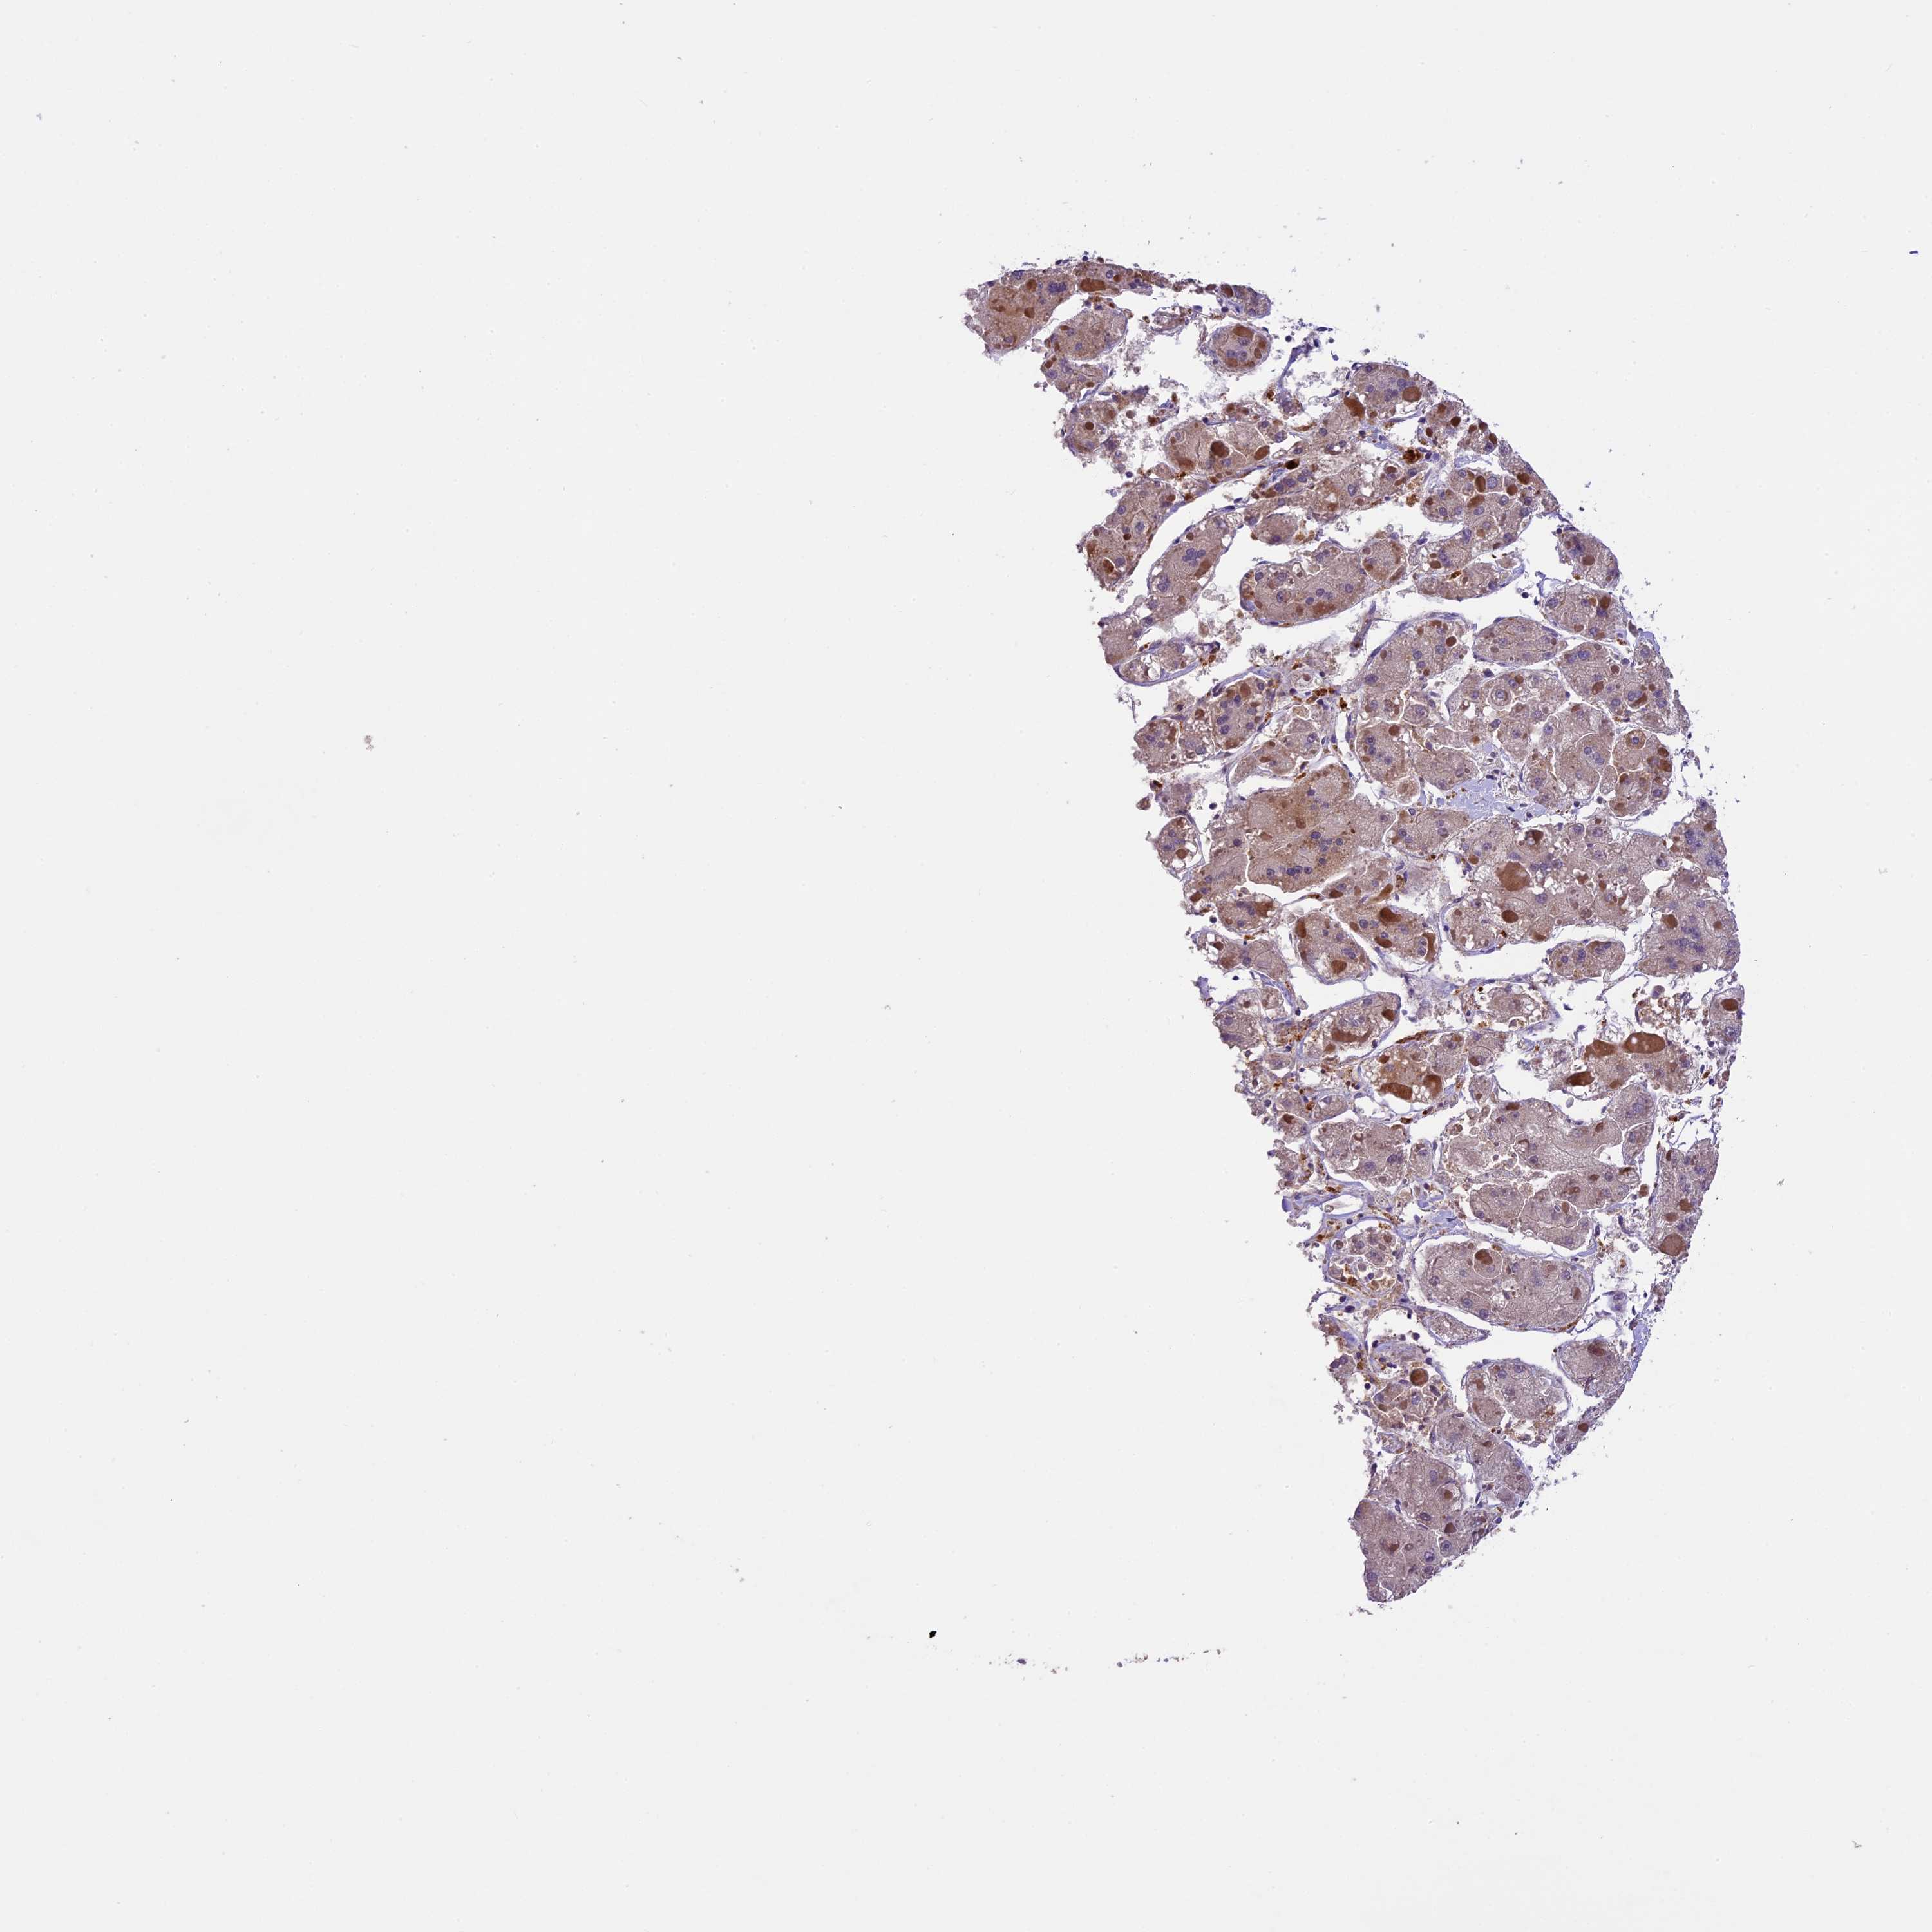

LIVER CANCER - Protein expressioni

A mouse-over function shows sample information and annotation data. Click on an image to view it in a full screen mode. Samples can be filtered based on level of antibody staining by selecting one or several of the following categories: high, medium, low and not detected. The assay and annotation is described here.

Note that samples used for immunohistochemistry by the Human Protein Atlas do not correspond to samples in the TCGA dataset.

Antibody stainingi

Antibody staining in the annotated cell types in the current human tissue is reported as not detected, low, medium, or high, based on conventional immunohistochemistry profiling in selected tissues. This score is based on the combination of the staining intensity and fraction of stained cells.

Each image is clickable and will lead to virtual microscopy that enables deeper exploration of all samples and also displays staining intensity scores, fraction scores and subcellular localization as well as patient and tissue information for each sample.

Antibody HPA039533

Antibody HPA040355

Staining

High

Medium

Low

Not detected

Intensity

Strong

Moderate

Weak

Negative

Quantity

>75%

75%-25%

<25%

None

Location

Nuclear

Cytoplasmic/membranous

Cytoplasmic/membranous,nuclear

Cholangiocarcinoma

Carcinoma, Hepatocellular, NOS